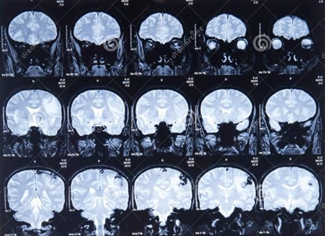

MRI也就是磁共振成像,英文全稱是:Magnetic Resonance Imaging。磁共振成像是斷層成像的一種,它利用磁共振現(xiàn)象從人體中獲得電磁信號(hào),并重建出人體信息。